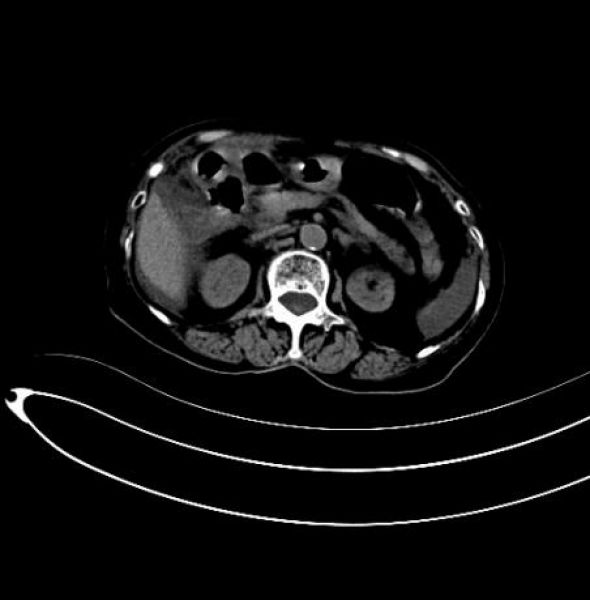

患者术前影像

该患者为什么不选择腔镜手术呢?因为患者胆囊穿孔致胆汁性腹膜炎,根据影响检查判断,患者腹腔明显大量胆汁性积液,通过腹腔镜是很难进行腹腔清洗的,患者术后快速康复的一个关键因素就是腹腔灌洗要充分,最大化减少术后腹腔胆汁残留。另外一个方面,患者急诊入院,呼吸情况不好,为减少气腹影响而快速完成手术,开腹也是最佳选择。作为一位成熟的外科医师,不能为了微创而微创,一定要综合分析,选择最有利于患者术后康复的治疗方案。